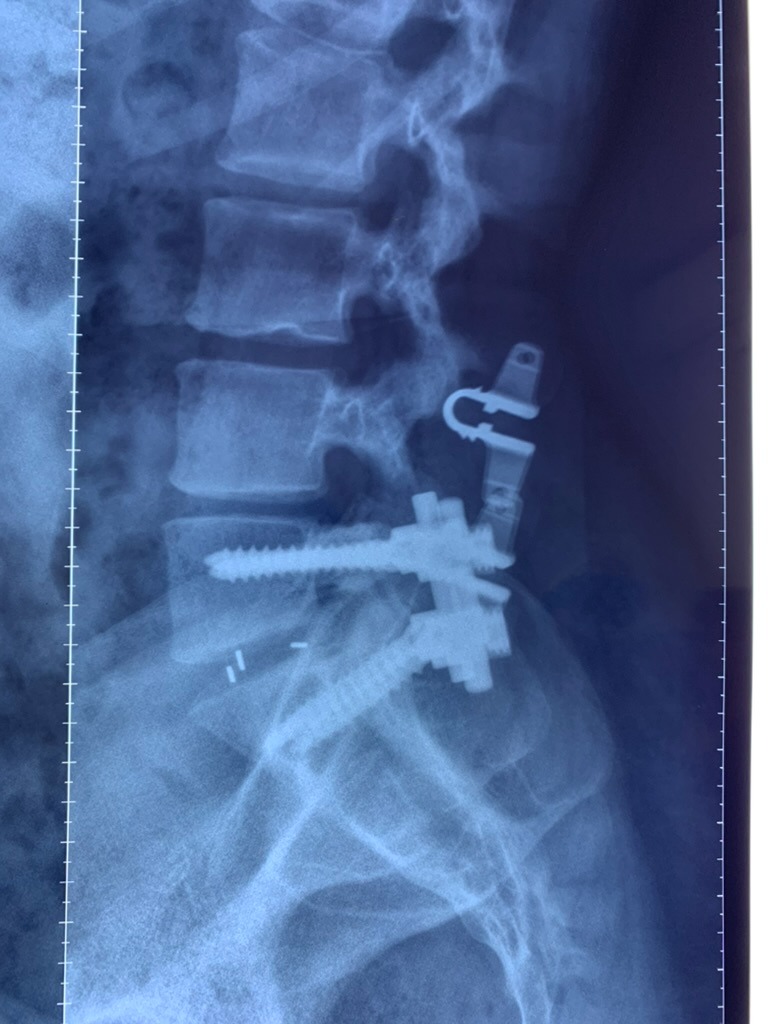

CIRUGIAS

RESULTADOS